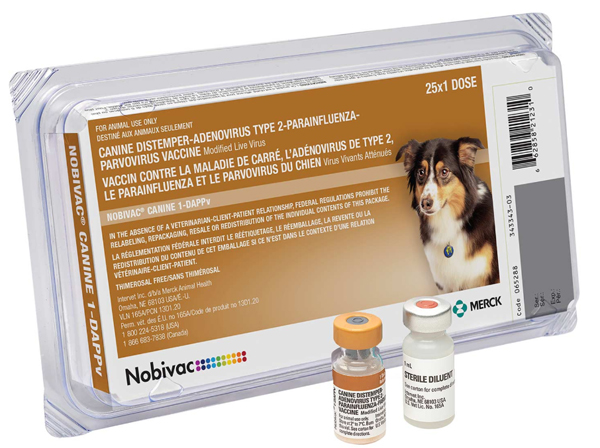

| Insert Date | Name | Dosage | Veccines file | Due Date |

| May 15, 2025 | Nobivac Canine 1-DAPPv | 1ML |

|

June 15, 2025 |